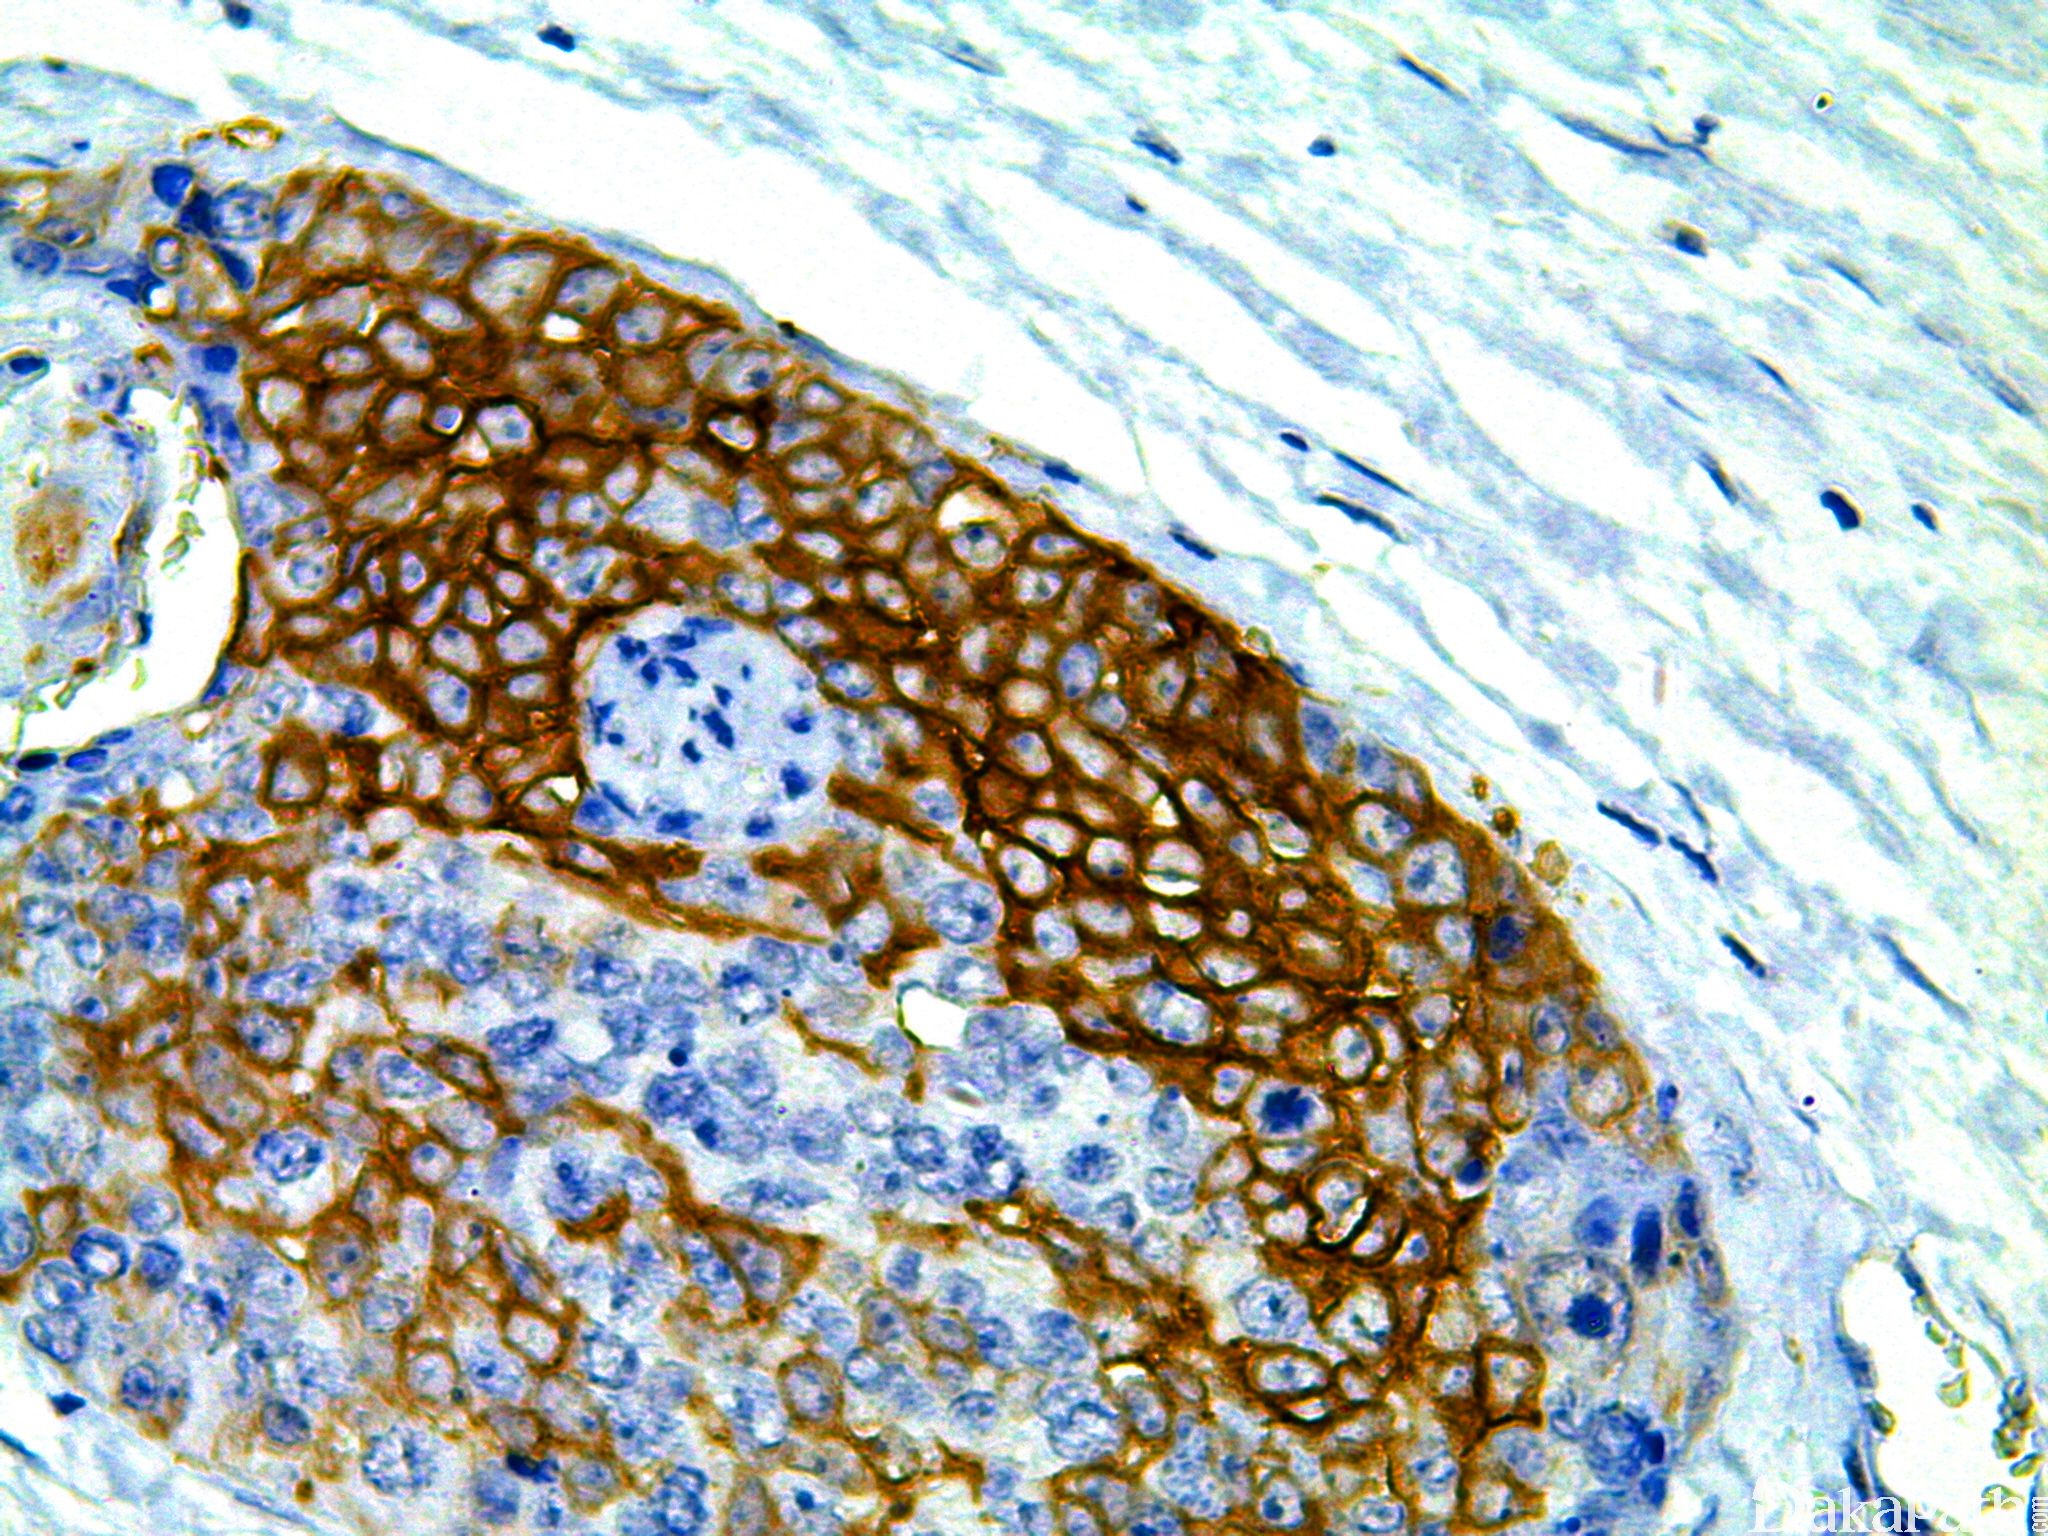

恶性肿瘤预后指标之一。目前用于肺非小细胞癌靶向治疗的参考。

信号定位: 胞膜、胞质(少)

1. 与肿瘤预后及靶向治疗有关,对肿瘤诊断意义不大;

2. 三阴性乳腺癌,通常染 EGFR 以指导治疗。